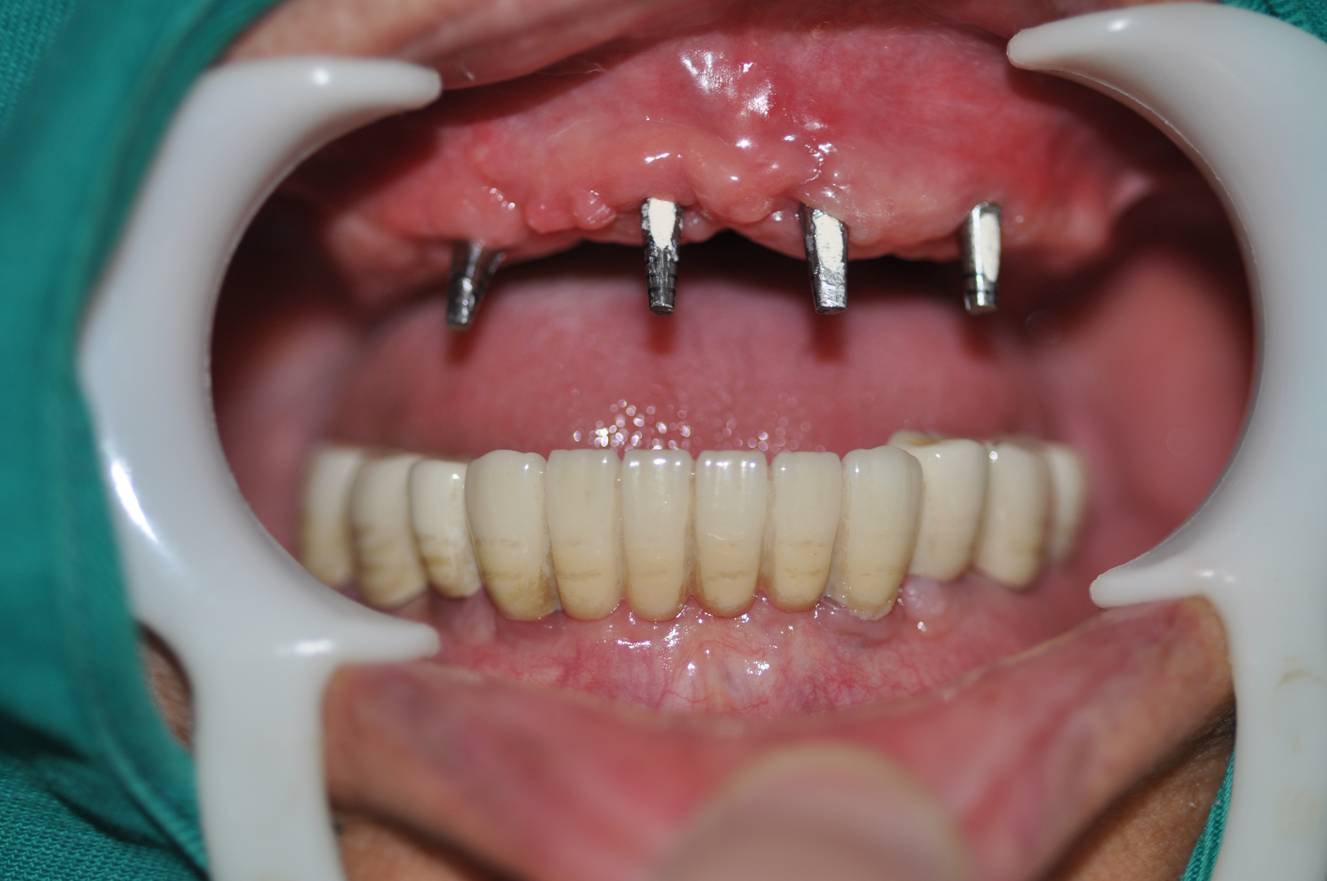

二、植入人工种植体

在局麻的状态下,将种植体植入患者的牙槽骨内。通常植入一枚需要10-30分钟。如缺牙部位骨量不足,则需植入人工骨粉材料进行补充。种植完成后,患者需要等待人工牙根和牙槽骨结合,大致需要2-6个月,这段时间可戴临时假牙度过。

植入种植体